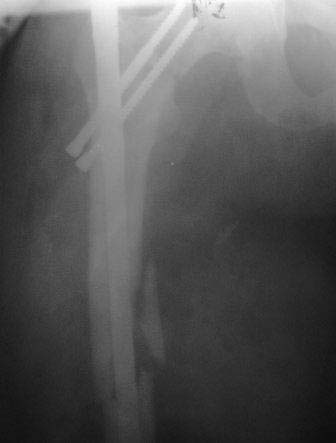

Добрый вечер уважаемые коллеги. На днях оперировал б-ного 36лет, с переломом шейки и диафиза бедра, травма высокоэнергетическая, ЭОП нет, оперируем под рентген контролем закрытым способом,т.е зона перелома не открывается, правда, получается долго. В общем в ходе операции все было хорошо и рентген контроль тоже, осталось только докрутить до конца винты, и после операции контроль.рентген ни делал, устал, и был уверен, что все нормально. На второй день у б-ного резко начали подниматься печеночные ферменты(АЛТ,АСТ)до 5-6 раз, ИФА-отр, гепатологи хотят перевести, и сделал Р-графию перед переводом. Осталcz варус, верхний винт упирается в сустав, что делать пока не знаю, может быть? винт немножко отвинтить и ждать! И тут же обратиться к Вам уважаемые коллеги! С уважением Абдурашид.

Что делать??? Конечно ресинтез - винты прошли мимо шейки и головки. И почему они еще не параллельны друг другу...

Добрый день коллеги! судя по представленным ренгенограммам имеет место базальный перелом шейки бедренной кости и спиральный клин с промежуточным фрагментом в области диафиза. имеется ряд проблем:

1)неадекватная репозиция и несоответсвующий фиксатор, при введении которого и появился варус.

2)Для остеосинтеза шейки выбраны неадекватные винты, один из котрых полнорезьбовой,а резьба второго перекрвает зону перелома.Поэтому ни о какой компрессии в зоне перелома речи быть не может

3) не исключено, что один из винтов введен мимо блокирующего отверстия, это объясняет асимметричное положение винтов в шейке, либо полнорезьбовой винт не соответствует величине отверстия гвоздя.